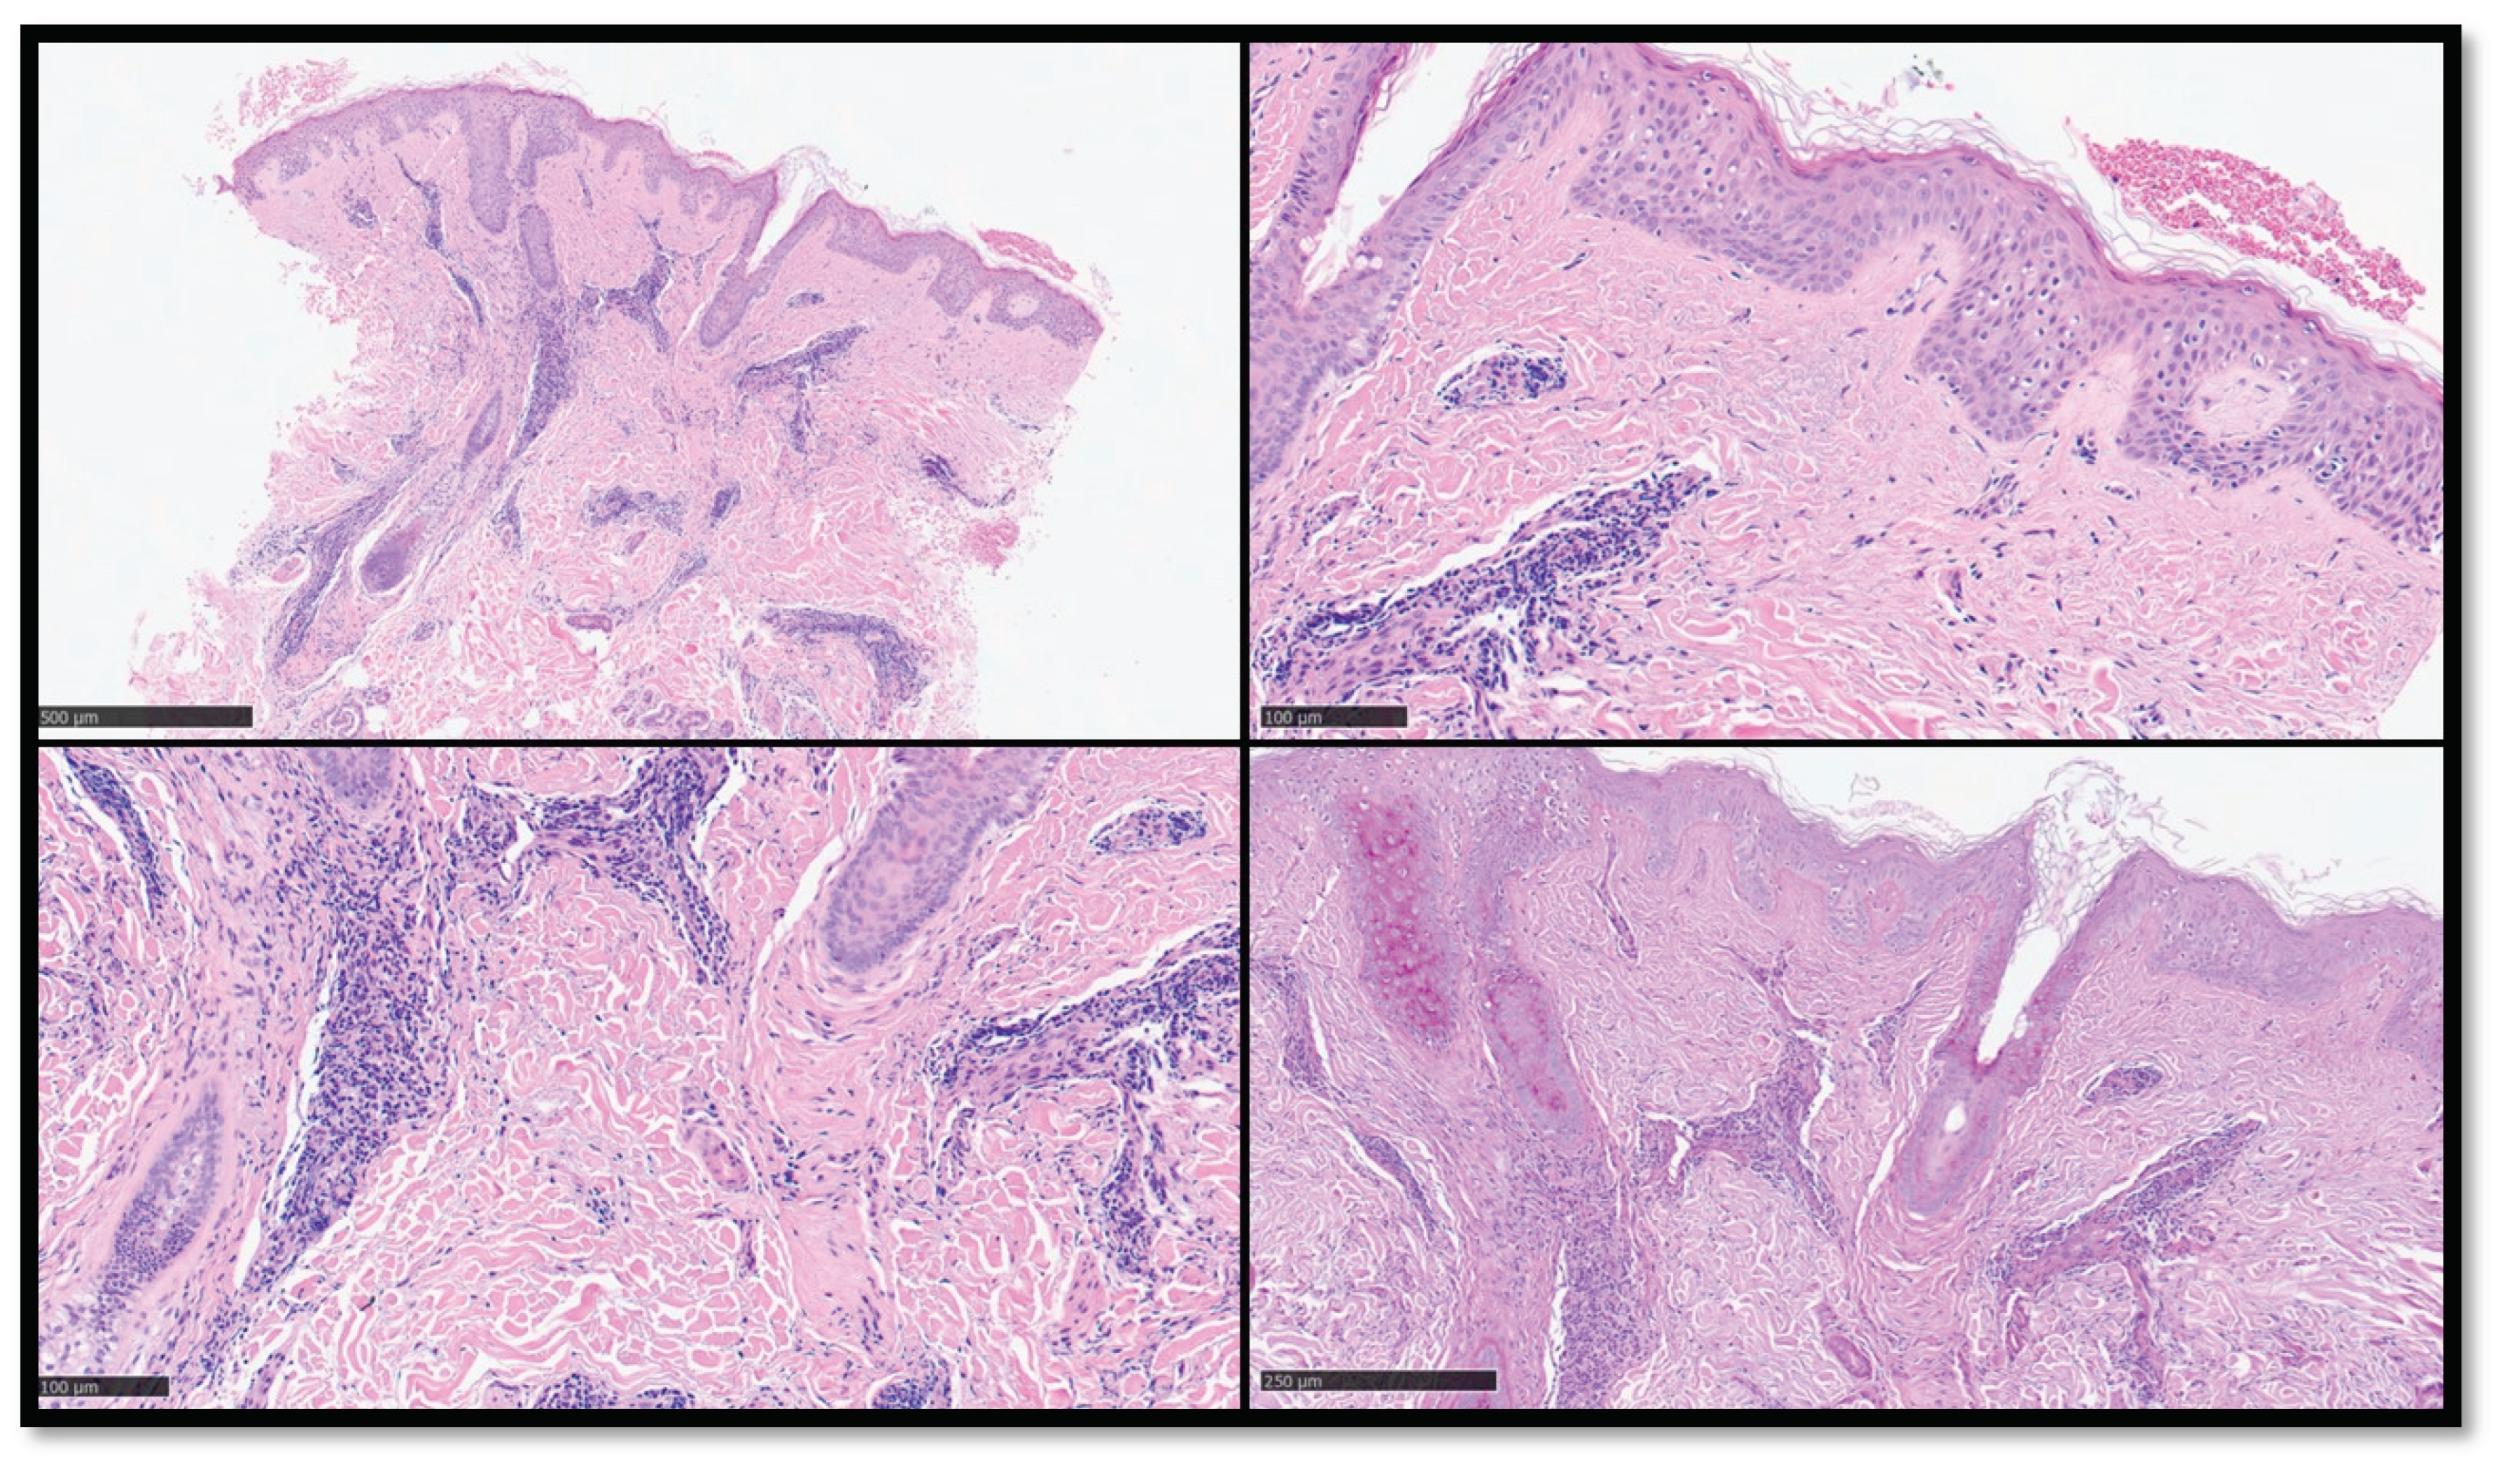

5. Histopathology